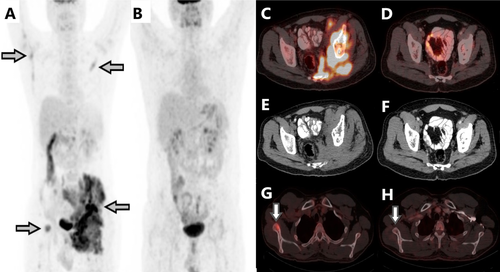

Interstingly, sequential FDG PET/CT scans over 3 years demonstrated partial metabolic response in primary and complete metabolic response (CMR) in the metastatic sites and post 3 years CMR at all sites. The high cumulative doses of Cy and Eto (over 5 g each) lead to the decision to stop the metronomic treatment and observe.